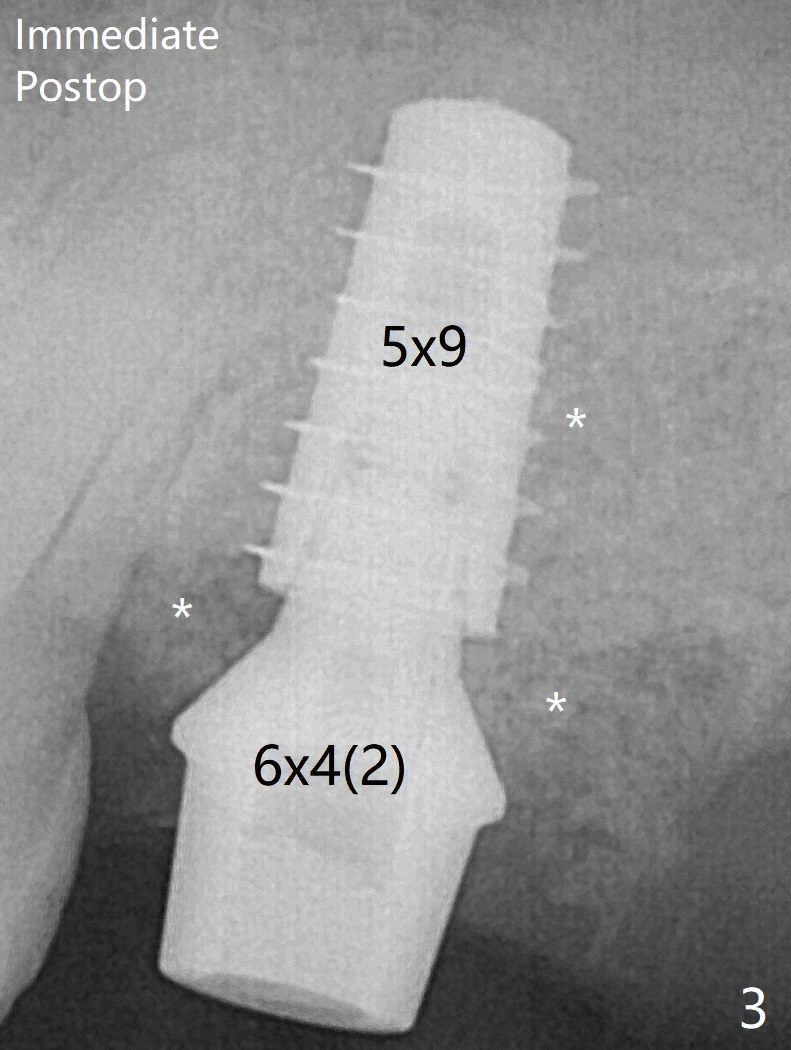

The 3 remaining sockets (Fig.1 *) around the final implant are filled with sticky bone (Fig.2 *).  The sockets are non-existing 1 year 7 months and 8 months postop (Fig.6,7 (BW)).